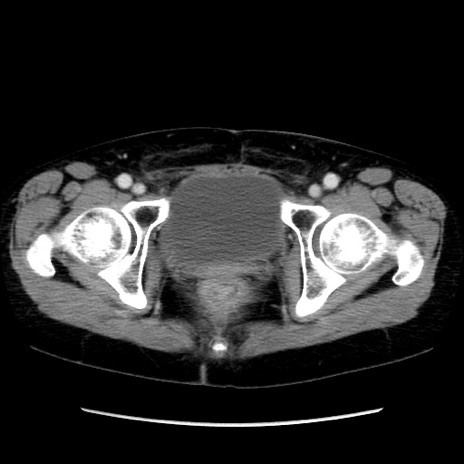

矢状断像

【症例】40歳代 女性

【主訴】上腹部痛、嘔気・嘔吐

【現病歴】約9時間前頃から急に上腹部痛、嘔気、嘔吐が出現。改善しないため救急要請。

【既往歴】子宮頚癌(広汎子宮全摘術、放射線療法)、腸閉塞

【身体所見】腹部:平坦、軟、腸雑音亢進、上腹部を中心に腹部全体に圧痛あり。

【データ】WBC 8400、CRP 0.03